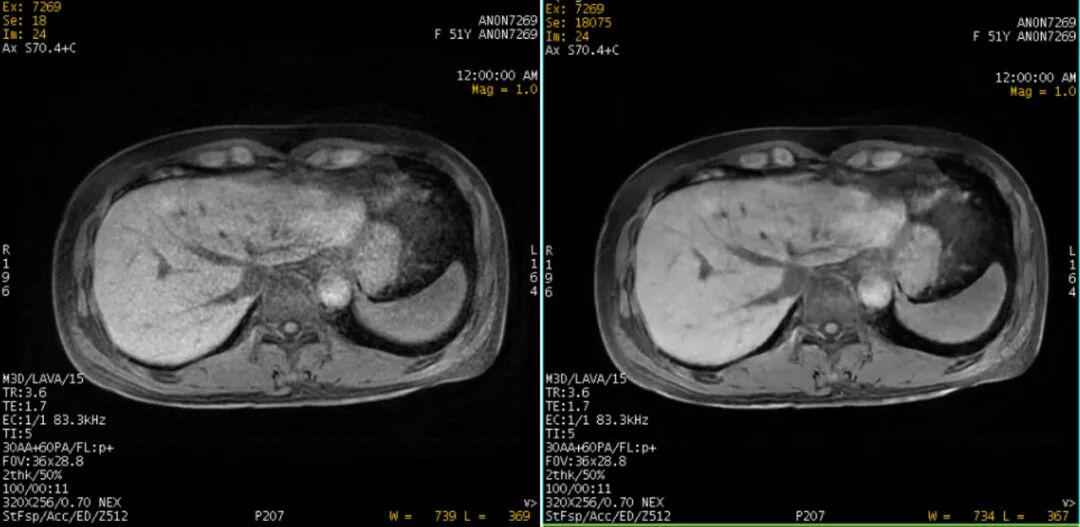

腹部极清成像– 有效去除模糊效应

除提升画质之外,IQE还能将特殊患者扫描成功率提高30%,减少患者流失,提升患者体验。总体来说,IQE的核心优势在于实现了快速、清晰和精准三者的完美结合。